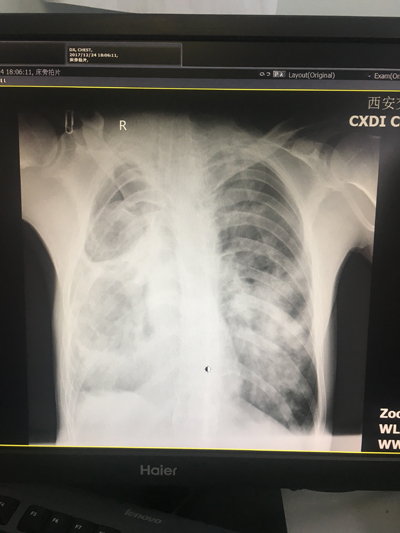

病史追问了解到该患者来急诊时,已出现严重低氧血症,血氧饱和度波动于30~45%之间,伴心率偏快,波动于120~150次/分,血压偏低,波动于90~110/45~60(去甲肾上腺素等血管活性药物维持),且烦躁不安,急诊抢救间予以紧急气管插管、转运呼吸机支持下收EICU。入院后予以镇静、镇痛并呼吸机控制通气,在高PEEP、高压力支持、纯氧下血氧饱和度仍波动于50~60%,血气分析提示PO2:36mmHg,Lac: 6.5mmol/L,查体双肺闻及广泛湿罗音,右侧为著;因患者病情危重,未能及时完善胸部影像学检查,但患者约1周前的CT提示右上肺脓肿、右下肺及左肺大致正常。经过综合分析,考虑患者为右肺脓肿扩散、继发急性双肺严重感染所致急性呼吸窘迫综合征(ARDS)。经过积极、高支持力度的机械通气,患者氧和改善不明显,张正良副主任通过综合评估后考虑患者病情极危重、若不能有效改善氧和即将出现生命危险,但目前的机械通气策略已无法满足要求,立即决定对患者采用V-V ECMO治疗,遂在向科室主任裴红红教授汇报、嘱立即进行有创血压监测等积极准备的同时,与患者家属进行充分沟通,患者家属了解后当即表态同意应用ECMO治疗。得益于急诊科多年来在ECMO团队建设方面的成效,从决定开展ECMO开始,科室ECMO流程立即启动、医护ECMO团队放弃休息,立即从西安市的东西南北齐聚科室,裴红红主任和柏玲护士长也在第一时间赶到医院,进一步共同评估病情、完善相关准备。为更有利于置管、减少对患者的损害,急诊科立即邀请B超室、放射科、胸外科、呼吸科等多科室会诊,协助评估血管情况、肺部情况等。床旁X片提示患者双肺弥漫性改变,符合ARDS影像学表现。

守候在旁的影像科值班医师也第一时间为患者做床旁X片,结果提示置管位置良好。